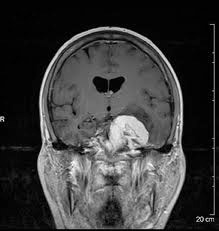

Not my brain, but similar tumor, opposite side.

and spreading them across steering wheel, I could see a lot of gray matter – like any picture of a brain- except one big difference, the white, oblong golf ball on the side. It looked big for my small brain. I searched for my name and date to be sure they were really pictures of my brain.